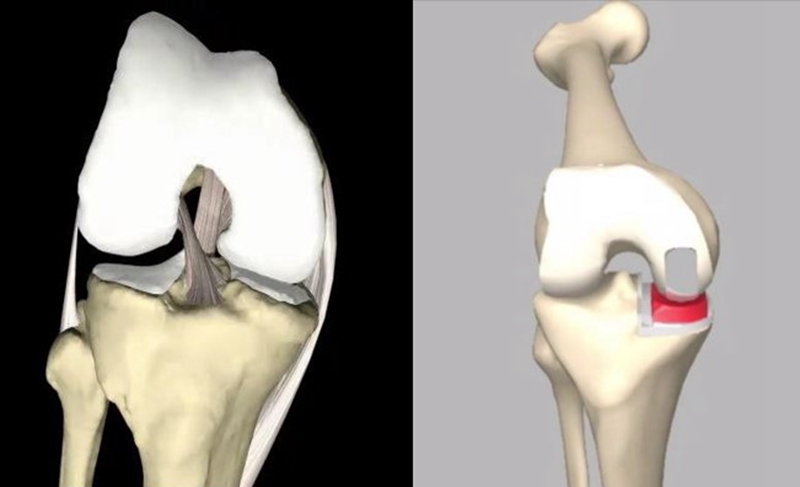

OUKA垫片的设计和稳定:

半月板-股骨(球-臼):屈伸运动;

半月板-胫骨(平-平):水平+旋转运动;

活动型垫片随股骨假体而运动。

锁扣机制:当股骨假体位置安放准确,衬垫对线良好,这种机制才有效

在膝关节最后伸直的15~20°;

垫片随股骨假体存在内旋;

垫片前内侧可超出胫骨平台前缘甚至悬空。

手术技术示意图

垫片移动轨迹测量